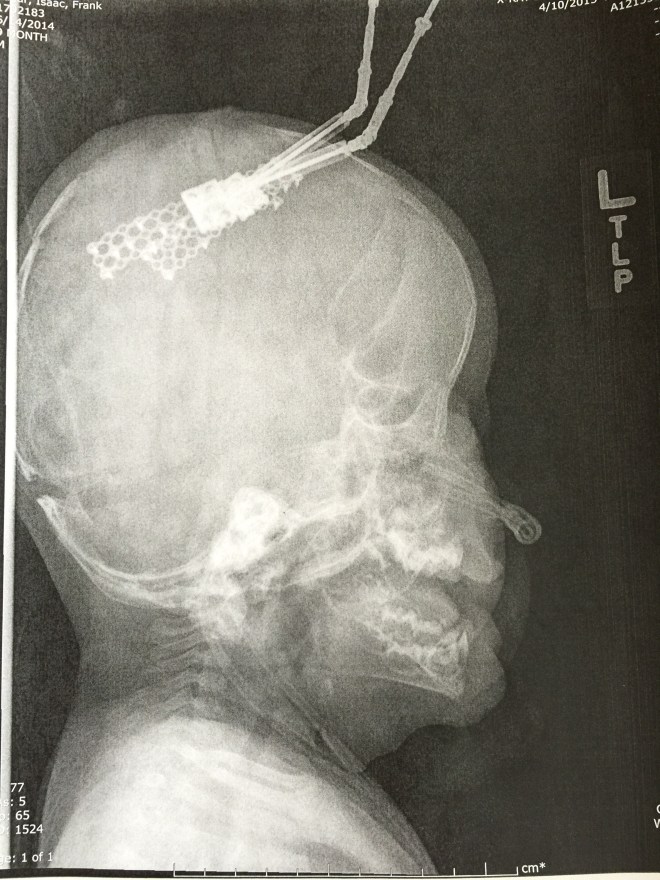

Isaac has been doing great. There was a concern a few weeks after we brought him home. Part of his incision had opened up and the surgeons were concerned that it wouldn’t heal on its own. They had contemplated going back in and closing it up and possibly taking out the plate that was in that area. They decided to give him another week to see if his body would heal up and avoid another surgery. Well, he must not want to go into surgery because the incision healed and the following week we were in they were able to remove the stitches. He does still have his Broviac Line and is still getting heavy antibiotics every night infused through the line. He will continue with the infusion antibiotics until his next surgery. He will be having surgery on his palate and his first finger release in about a month or two. We are still waiting to hear from the scheduler on a date.

The Craniofacial department has a camera that takes a 3D picture. These next two pictures show a comparison of Isaac’s head from the beginning of May, before his last surgery. The pictures on the right are from May and the pictures on the left are from a few weeks ago. You can really tell a difference in the shape of his head.